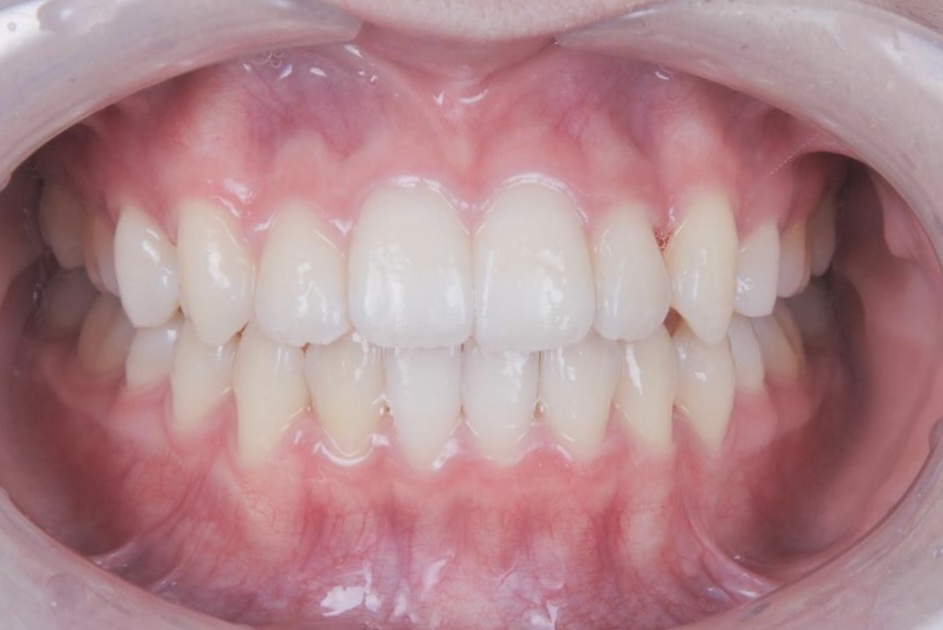

八重歯や噛み合わせが整い、口元の印象が大きく改善しています。治療後には、矯正中のモチベーション維持や経過確認がしやすかった点、想定よりも早く治療を終えられたことについて、嬉しい口コミもお寄せいただきました。

AFTER